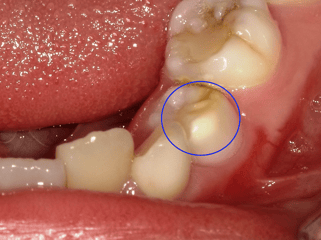

4.生えたての永久歯の特徴

生えたての永久歯の歯の溝は図で示す通り、細く深い溝があります。

この溝の中は歯ブラシの毛先が届かないため、酸性の状態が長く続くと虫歯になってしまいます。

生えてからいい状態が続くとこの溝は唾液中のミネラルの結晶が沈着して埋められ、虫歯になりにくくなります。

また生えたての永久歯のエナメル質はもミネラルの含有量が少ないため酸に歯が溶けやすく虫歯になりやすいです。この件も生えてからいい状態が続くと唾液中のミネラルが取り込まれてさらに虫歯になりにくくなります。